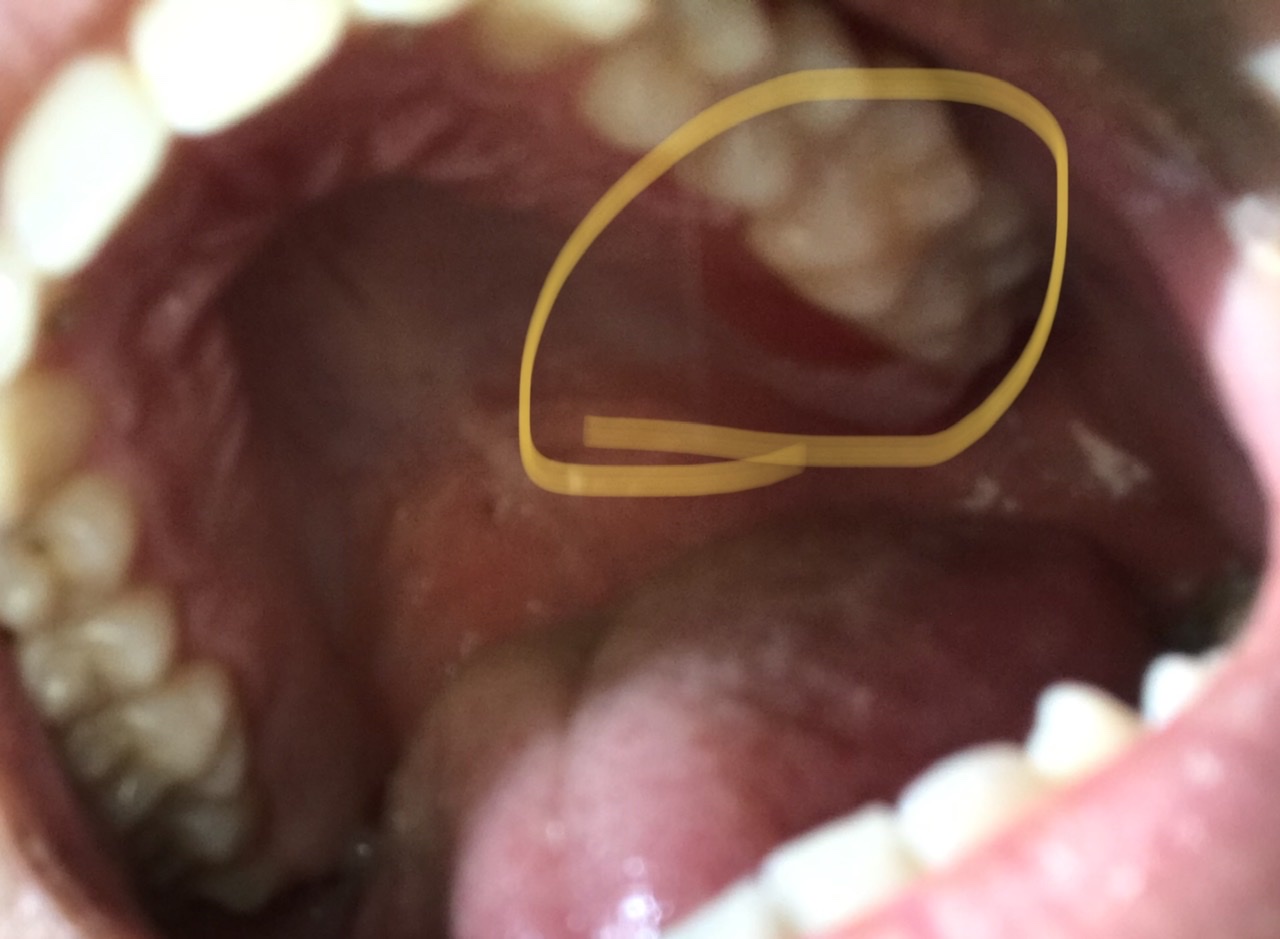

Domande di Dentisti-Italia.it | Pag. 98 (da 131 a 135)